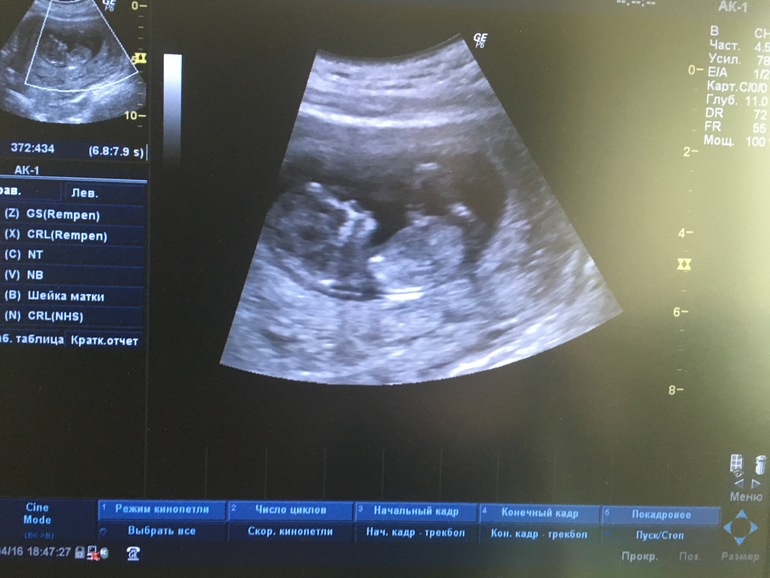

Ну вот был у нас сегодня первый скрининг.

Сердце 168 уд.

Ктр 58,0мм.

Толщина воротникового пространства 2,0мм

БПР 20,0мм

Венозный проток 0,830

Хорион по передней стенке перекрывает внутренний зев.

Кость носа определяется.

Все органы в порядке. Ручки ножки. 😊😊😊